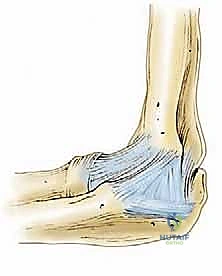

- تحرير المحفظة الأمامية (Anterior Capsulectomy): باستخدام أدوات دقيقة (Shaver & Radiofrequency)، يتم قطع وإزالة الجزء الأمامي من المحفظة المفصلية المتليفة التي تمنع المرفق من المد (Extension).

- استئصال النتوءات العظمية (Osteophyte Resection): يتم استخدام مثقاب دقيق (Burr) لبرد وإزالة الزوائد العظمية في الحفرة الإكليلية (Coronoid Fossa) والحفرة الزجية (Olecranon Fossa) لفتح المجال لحركة العظام.

- تحرير المحفظة الخلفية (Posterior Capsulectomy): ينتقل الجراح إلى الجزء الخلفي من المفصل لإزالة التليفات التي تمنع الثني (Flexion).